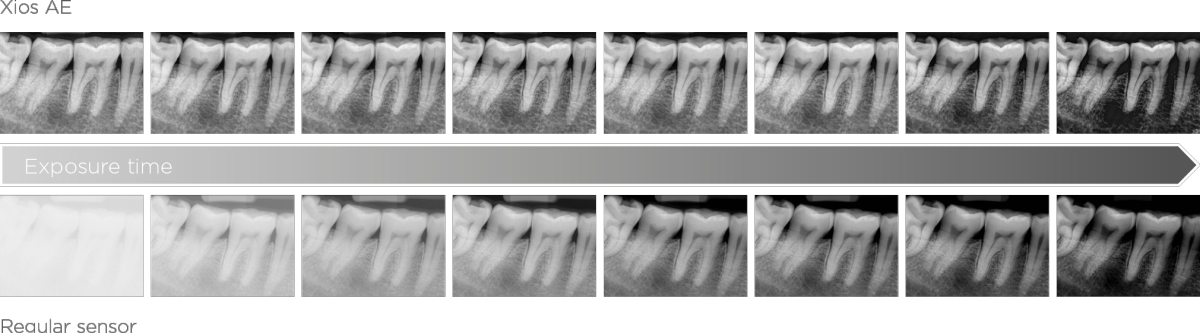

Xios AE sensors support a high level of clinical performance with superior image quality and advanced filtering enhancements in order to highlight relevant anatomical structures to support an accurate and detailed diagnosis. Low-noise images, improved visibility of details, and dedicated filtering in indications such as endodontic cases or tooth decay, provide a relevant advantage in diagnostic certainty and help to aid true confidence in the treatment assessment. When combined with smart connectivity between the hardware and Sidexis 4 software and a modular system to accommodate each and every patient and situation in order to help facilitate an exceptional experience for both the patient and the user, you get the perfect partner for any practice.